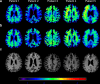

Magnetic resonance-guided focused ultrasound in combination with intravenously injected microbubbles has been shown to transiently open the blood-brain barrier, and reduce beta-amyloid and tau pathology in animal models of Alzheimer's disease. Here, we used focused ultrasound to open the blood-brain barrier in five patients with early to moderate Alzheimer's disease in a phase I safety trial. In all patients, the blood-brain barrier within the target volume was safely, reversibly, and repeatedly opened. Opening the blood-brain barrier did not result in serious clinical or radiographic adverse events, as well as no clinically significant worsening on cognitive scores at three months compared to baseline. Beta-amyloid levels were measured before treatment using [18F]-florbetaben PET to confirm amyloid deposition at the target site. Exploratory analysis suggested no group-wise changes in amyloid post-sonication. The results of this safety and feasibility study support the continued investigation of focused ultrasound as a potential novel treatment and delivery strategy for patients with Alzheimer's disease.